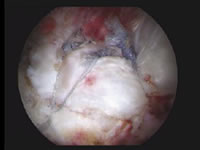

Schultergelenksspiegelung (Arthroskopie): degenerativer Sehnenriss